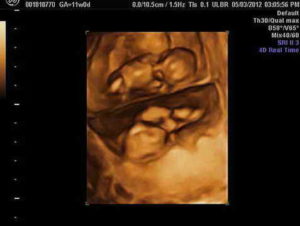

Беременности двойней по неделям не очень сильно разнится в зависимости от типа двойни. Однако определить, кто же родится — близнецы или двойняшки — сможет только исследование УЗИ. На каждом этапе беременности женщина должна подходить к своему здоровью и здоровью будущих малышей ответственно, своевременно посещать врача-гинеколога, и получать у него консультации.

Начиная с 5 недели УЗИ точно показывает, что будет двойня. Следует отметить, что на поздних сроках на УЗИ скорее всего уже не будет видно двойни, т.к. луч УЗИ видит только одного ребенка, расположенного ближе.

На восьмой неделе определить, что будущая мама ждет двух малышей, возможно только с помощью УЗИ матки.